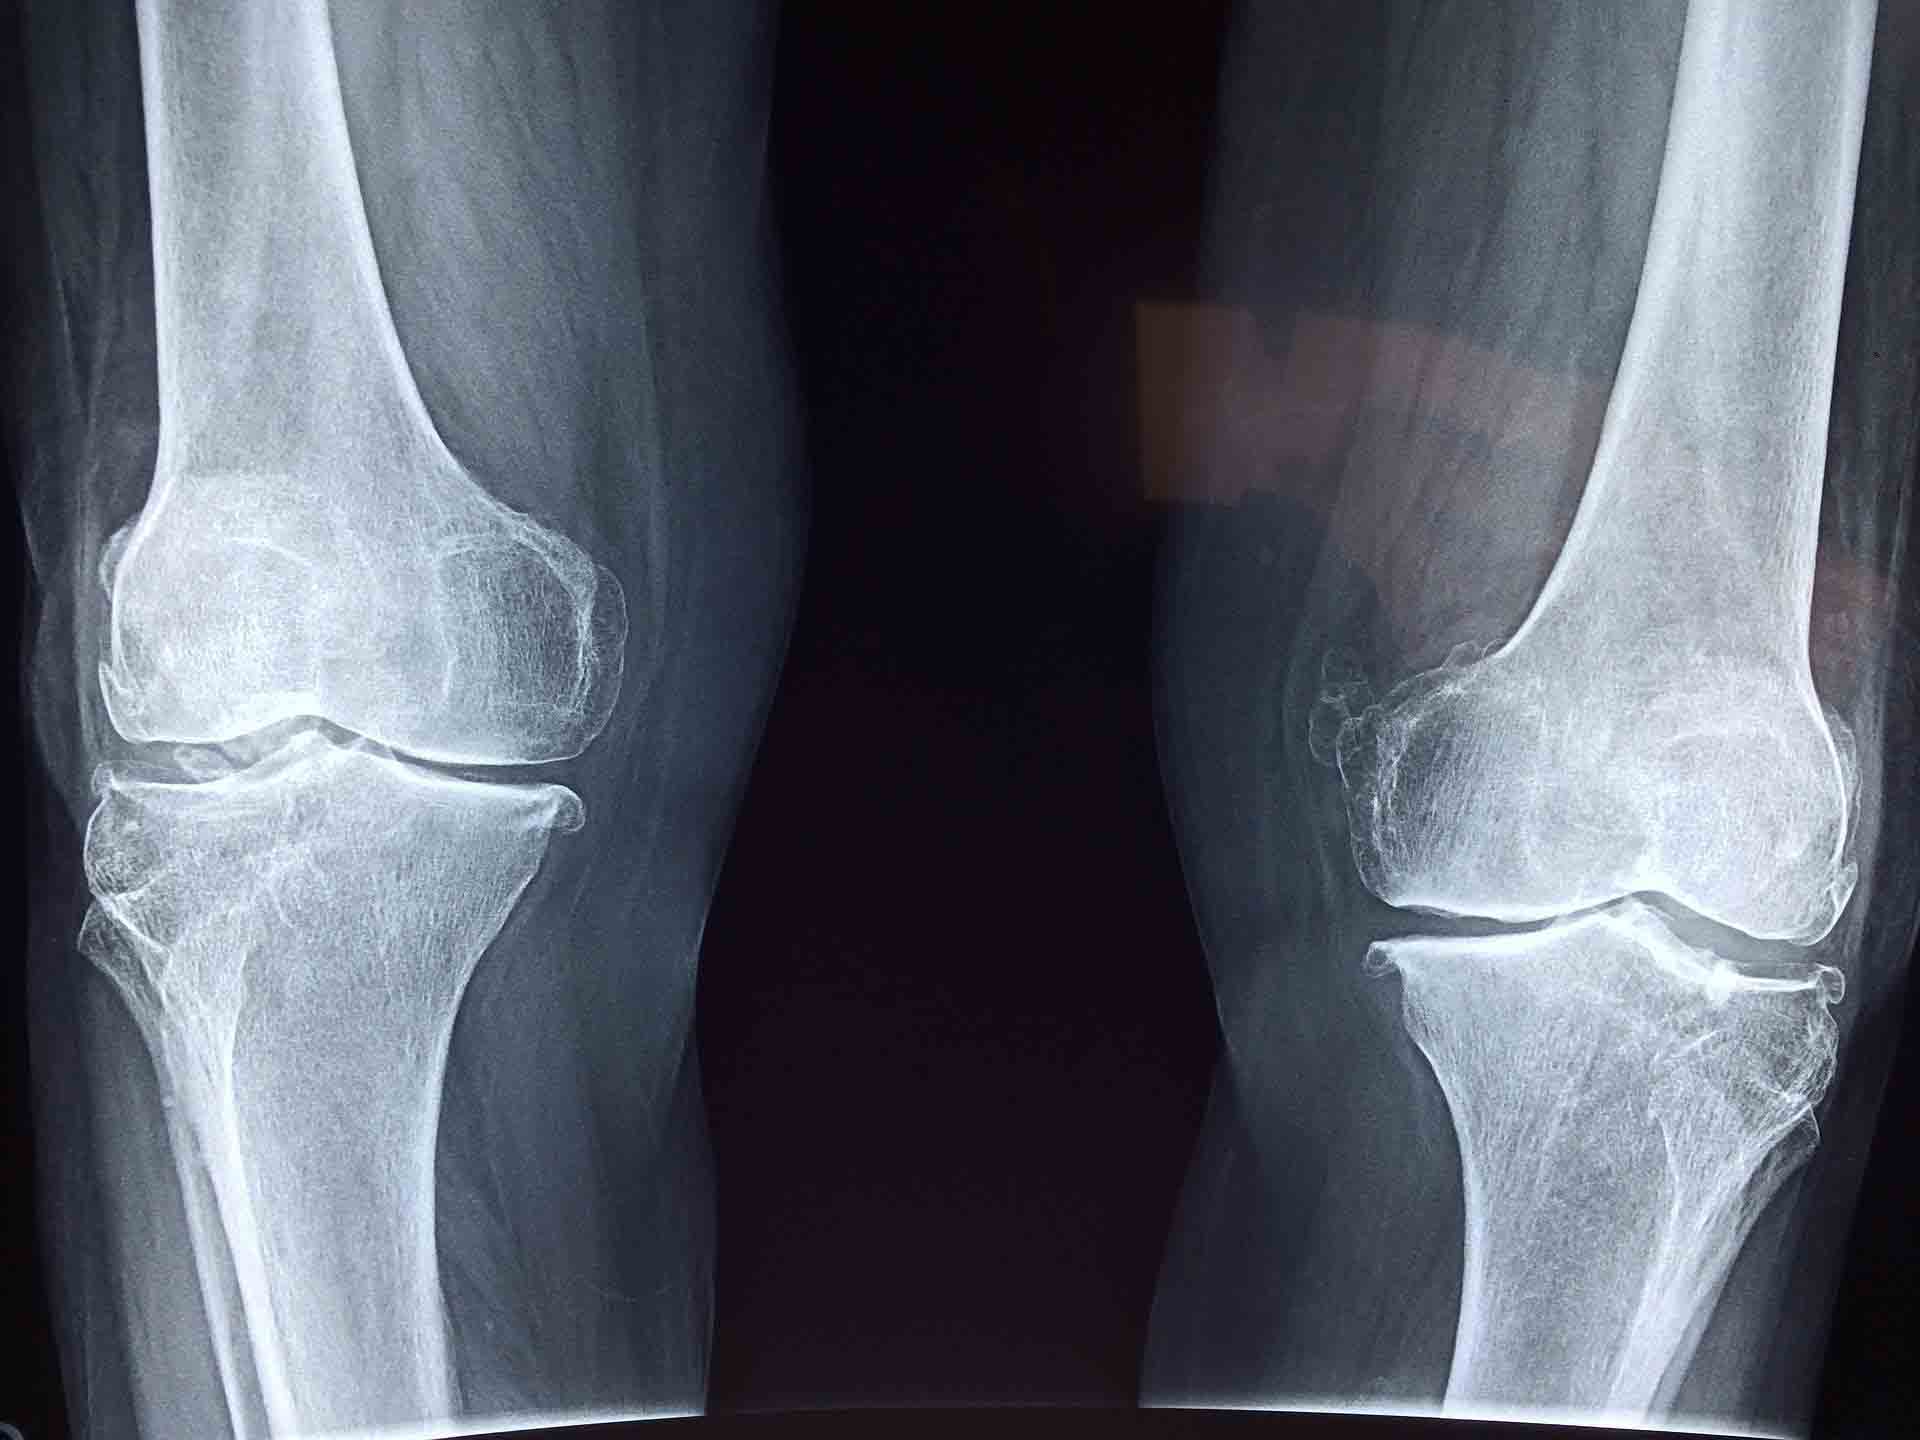

Artróza kolene (gonartróza)

Většinou postihuje obě kolena a častěji trápí ženy vyššího věku. Typickým příznakem bývá bolest při námaze, zejména při chůzi po schodech, případně při pohybu v obtížném terénu. Bolest zde mívá tzv. startovací charakter – objevuje se ráno či po dlouhém sezení. Po delším pohybu pak mizí, ale může se znovu objevovat při větší námaze kloubů.

V pokročilejším stadiu gonartrózy je bolest silnější a projevuje se i v klidu. Následně dochází k omezení hybnosti v kolenním kloubu, kdy pacientovi způsobuje potíže i pouhá chůze. Kloub bývá oteklý, může se tvořit větší náplň kolene, kdy jej musíme opakovaně punktovat a mohou se vyskytnout i deformity.

1. stupeň – chrupavka se ztenčuje, důsledkem čehož je zužování kloubní štěrbiny.

2. stupeň – nadále dochází ke zužování štěrbiny, kloubní plochy mohou obsahovat drobné nerovnosti, dochází k tvorbě osteofytů a přítomna bývá i sklerotizace.

3. stupeň – v této fázi se kloubní štěrbina stále zužuje, dále vznikají osteofyty, objevit se mohou i další problémy jako subchondrální skleróza či deformace kloubní jamky a hlavice.

4. stupeň – kloubní štěrbina úplně vymizí, na koncích kloubů jsou patrné deformace, objevují se i osteonekrotické změny, subchondrální skleróza, cysty a nadále též osteofyty. V této fázi přestává kloub fungovat.